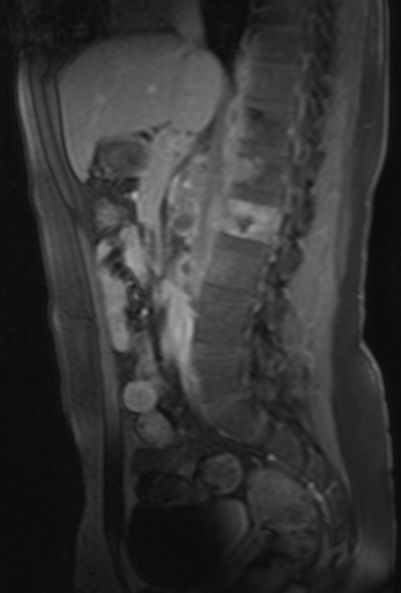

Rezidiv 1 Jahr nach follikulärem Lymphom

MRT